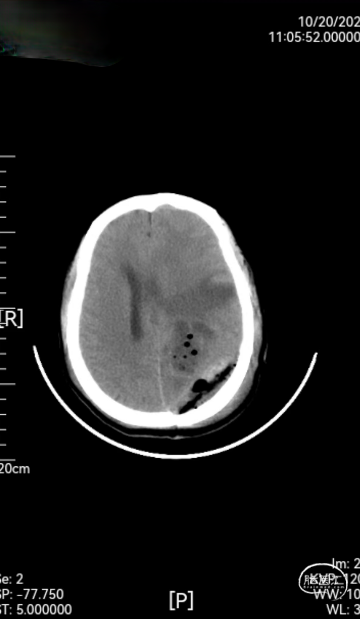

➤ 术后检查:术后第2天,第8天,第12天复查头颅CT(如图3),术后术区无渗血,骨瓣固定良好,无错位及膨出,且CT无伪影,患者顺利出院。

图3:术后第2天,第8天,第12天复查头颅CT